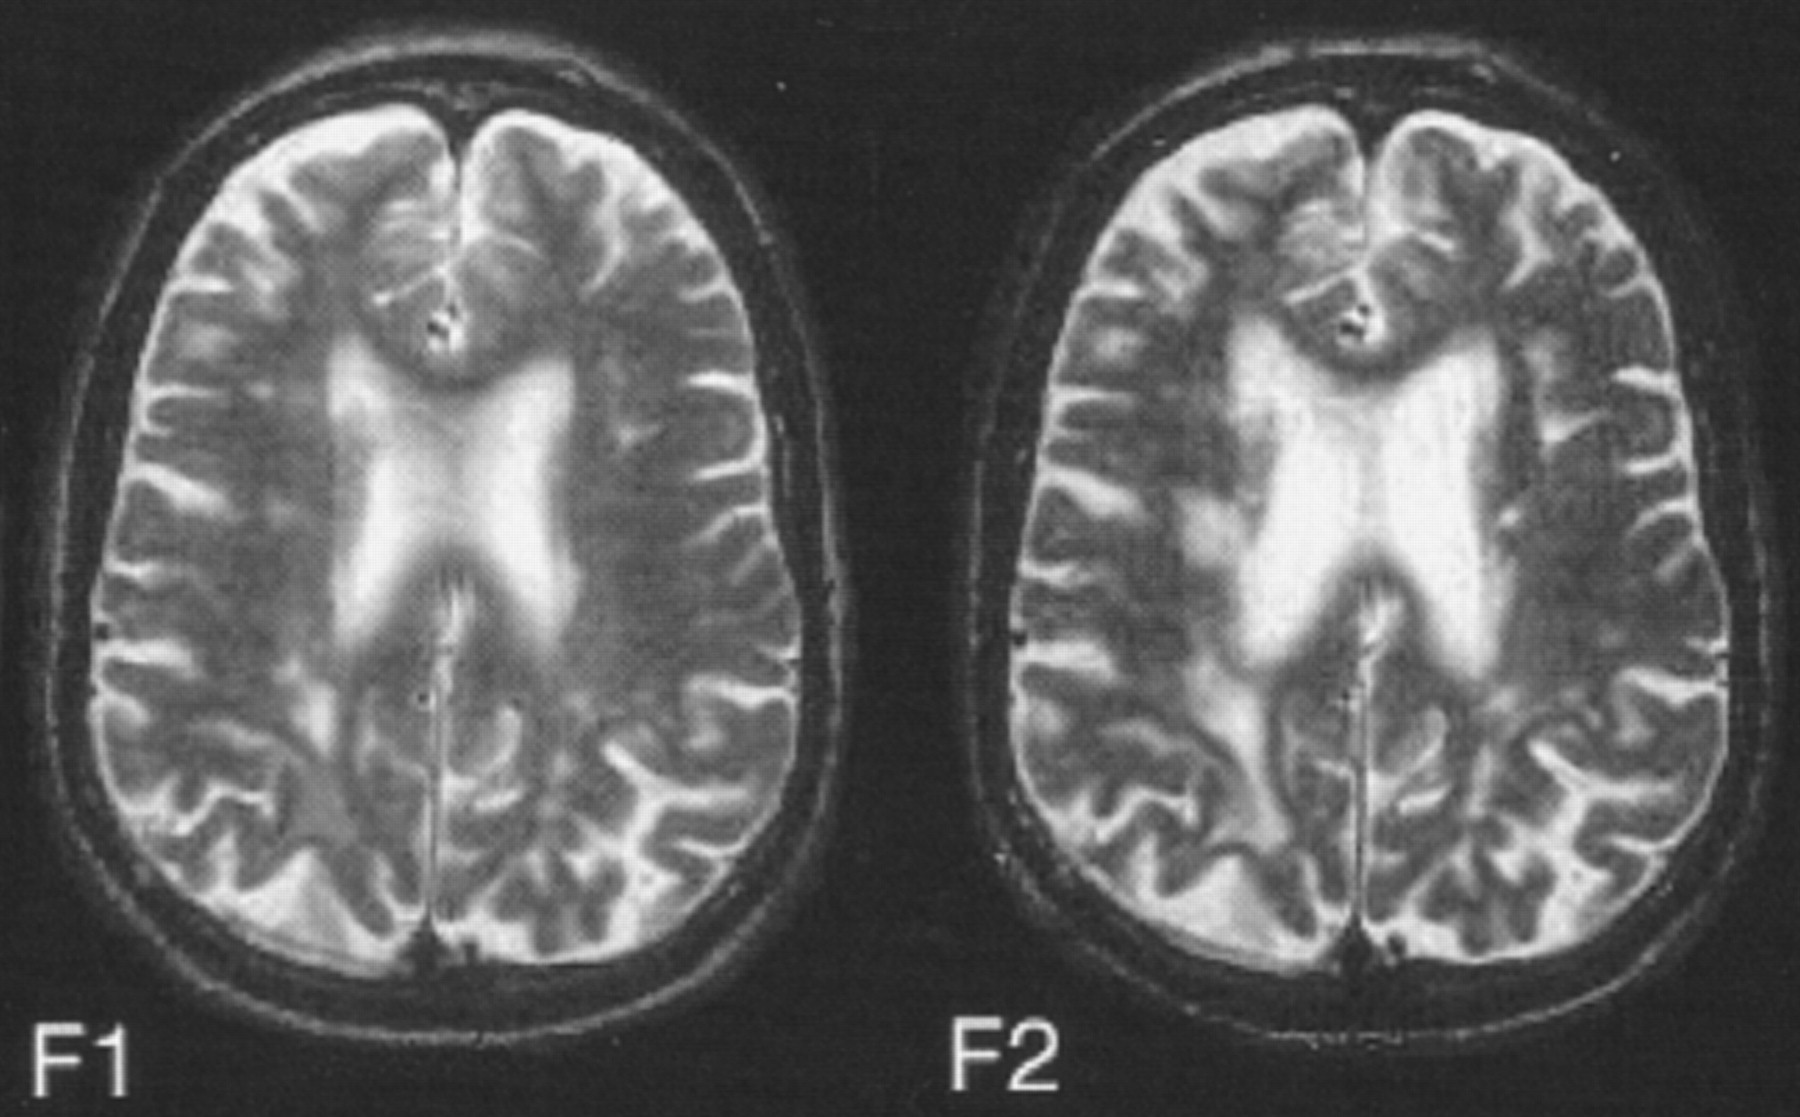

白质hyperintensities和平衡失调

惠特曼et al。跟踪调查了70名健康的老年人,发现一个重要的体积关系恶化的平衡和增加白质高密度核磁共振。这是第一个纵向研究表明hyperintensity体积变化与老年人步态和平衡的变化。

看到页面990年